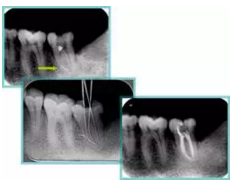

6. 鈣化

常見有修復(fù)性鈣化和增齡性鈣化。下面為根管鈣化 X 線片。

7. 器械折斷

右圖及下圖為器械折斷的 X 線片。箭頭處示折斷器械。